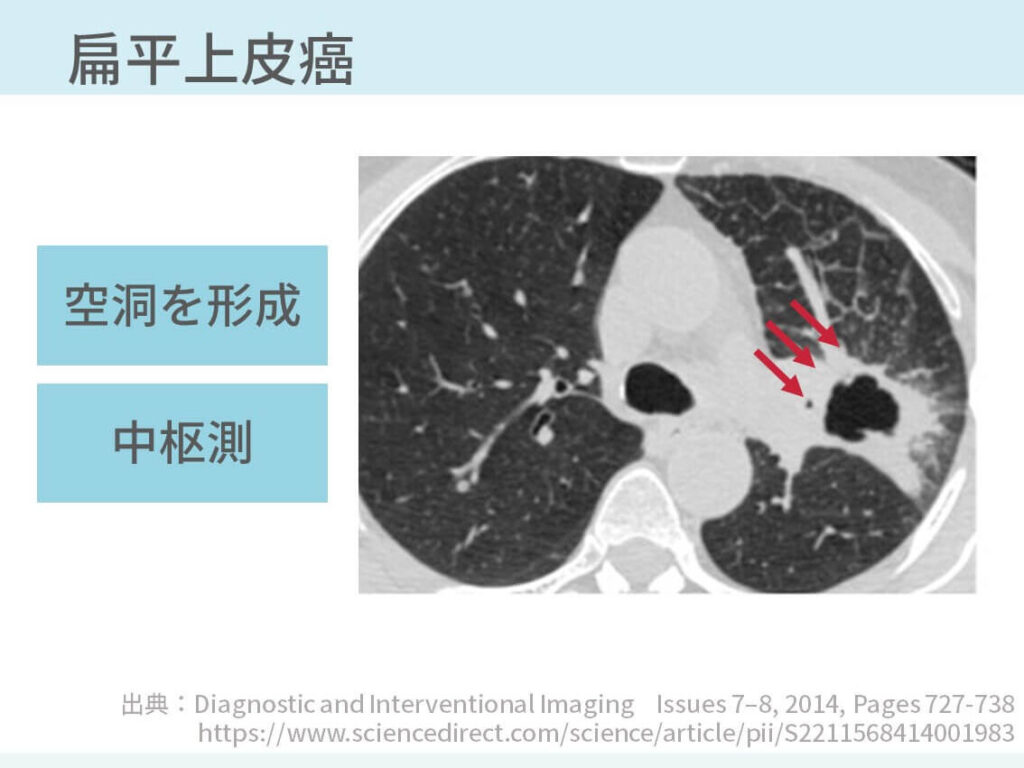

胸部のCT 第4版 | 村田喜代史, 上甲 剛, 村山貞之, 酒井文和 |本。胸部のCT 第4版 | 村田喜代史, 上甲 剛, 村山貞之, 酒井文和 |本。CC3 胸部CTの読影 - YouTube。kokuu 雑穀米 ホワイトブレンド グルテンフリー 2袋。CANON社製新型CT装置を導入 | 新柴又駅前クリニック(脳神経外科)。腹部CTを読影する上で重要な脂肪ウインドウとは? - YouTube。胸部CTの読影の基礎【働くのに必要な知識を最短で習得する方法。胸部CT画像の読影を支援するEIRL Chest CTの販売を開始 - エル。見逃しを防ぐための腹部CTの読影の順番|ごろ〜にゃ@放射線科医。18203920 | 腹部CT CBT | M3E Medical。体幹部領域-Aquilion PRIMEの各領域における技術 - 東芝。CT¹⁾検査|検査ガイド|患者さん向けガイド|原三信病院。腹部CT検査 胆石 - 医療のイラスト・写真・動画、素材販売サイト。胸部と腹部のCTに関する専門書、最新の知見を網羅。- 書籍名: 胸部のCT 第4版- 書籍名: 腹部のCT 第3版- 出版社: MEDSi- 書籍の状態: 良好- ISBN: 9784895921877- ISBN: 9784895921860ご覧いただきありがとうございます。○バラ売り希望にも対応します。(価格は応相談)コメントください!○未使用ですが、自宅保存のため運搬による傷が少しあります。○未使用のためメモなどはありません。カバーも目立った傷はありません。○できるだけ早く発送します。お急ぎの方はコメントください。